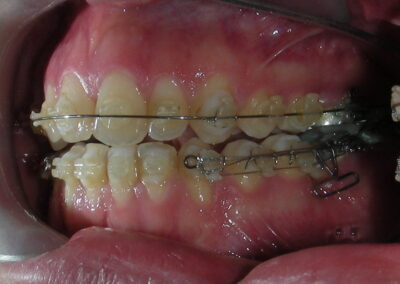

The upper brackets were bonded solely for the purpose of providing stability to the utility arch . Following the hierarchically structured treatment plan, we proceed with the alignment and leveling phase in order to enable mesialization of the posterior segments using sliding mechanics, which works effectively in conjunction with Roth prescription brackets .022.

A progressive archwire sequence was used for alignment, leveling, and three-dimensional control.

- .018″ × .018″ Blue Elgiloy sectional archwire was placed in three segments in the maxillary arch to maximize the effectiveness of Class II intermaxillary elastics, in conjunction with space closure (mesialization) in the mandibular arch.

- 017″ × .025″ Blue Elgiloy sectional leveling archwire beetwen # 35-37 and 45-47

After two years of treatment using appropriate biomechanics, the overbite was successfully corrected from -8 mm to +1 mm, achieving complete closure of the anterior open bite without exacerbating the patient’s lower facial third vertical proportions. At this stage, occlusal contacts were verified using articulating paper, and functional movements of the canines and incisors were evaluated to ensure proper anterior guidance and disclusion patterns. The patient was then referred to speech therapy (myofunctional evaluation) as part of the pre-debond assessment protocol.